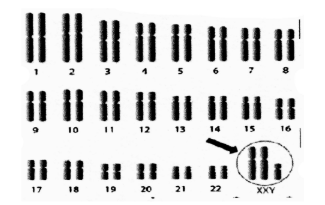

(II) Study the karyotype given below and answer the questions that follow.

(a) What is this disorder known as?

(b) How many chromosomes are present in the individuals with this disorder?

(c) State one typical feature of this syndrome.

Ans:

- Klinefelter’s syndrome

- This individual male has 47 chromosomes with an extra X chromosome.

- A typical feature of this syndrome is being tall and mentally retarded.